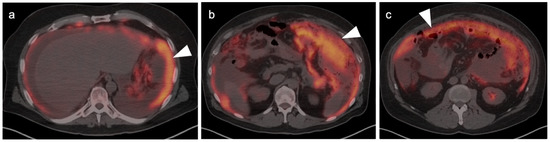

9. Bowel Adenocarcinoma: Colon, Rectum, Small Bowel

10. Anal Carcinoma